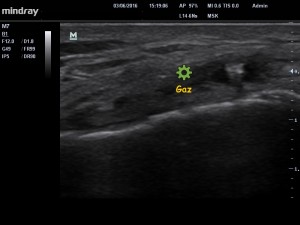

Le traitement a consisté dans un premier temps à « électrolyser » le contenu de ce kyste sous contrôle échographique (image 2). L’électrolyse permet la formation de NaOH (soude biologique) qui a pour effet de détruite et de liquéfier le kyste , et à la formation de Cl2 et de H2 qui sont des gaz apparaissant « blanc » en échographie (image 3) confirmant la bonne exécution de la procédure .

image 3. Visualisation du « gaz » formé par électrolyse.